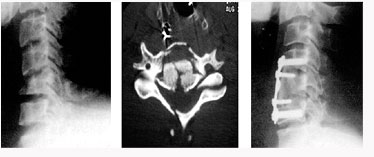

척추관 협착증의 방사선 소견

후방 요추체간 유합술 (PLIF) : 광범위한 후방 감압술 후 추간판(디스크)을 제거한 후 골이식을 시행하여 추체간 유합을 얻는 것

- 후외방 유합술에 비해 절개가 적다

- 신경근에 대한 충분한 감압이 이루어진다

- 추간판(디스크)로 인한 동통 및 재발이 없다

- 추간판 높이를 정상으로 회복시켜 준다

- 척추 정렬을 정상으로 회복시켜 준다

* 현재에는 최소 침습적인 방법으로 적은 절개를 통해 가능하다

전방 요추체간 유합술 (Anterior Lumbar Interbody Fusion)